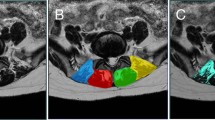

The cross-sectional area (CSA) and functional cross-sectional area (FCSA) of the PM, QL, MF, and ES were assessed at the mid-disc level of all lumbar spinal segments (Fig. 1). Due to measurement limitations, the PM muscles were evaluated from L1/2 to L5/S1 and the QL from L1/2 to L3/4. FI was calculated using the formula FI = ((CSA − FCSA)/CSA)*100. Three key indices were used to assess paraspinal muscle asymmetry: the CSA asymmetry Index (CAI), FCSA asymmetry Index (FCAI), and FI asymmetry Index (FIAI). These indices quantify the asymmetry between the left and right sides of the muscles:

MRI of a subject’s lumbar spine and target muscle measurements. (A) Sagittal view of the lumbar spine, with the yellow line indicating the location of the measured cross-sectional MRI; (B) Cross-sectional area of the psoas major (PM), quadratus lumborum (QL), multifidus (MF), and erector spinae (ES) at the L1/2 segment; (C) Functional cross-sectional area of the PM, QL, MF and ES at the L1/2 segment. LPM left psoas major, LQL left quadratus lumborum, LMF left multifidus, LES left erector spinae, RPM right psoas major, RQL right quadratus lumborum, RMF right multifidus, RES right erector spinae.